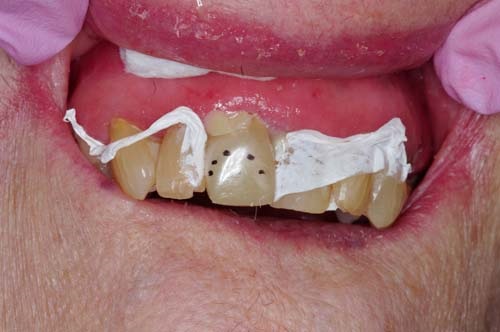

The 94-year-old patient in my chair had a fractured maxillary incisor (Figs. 1 and 2). Although her physical health was good and her basic systems were sound, she suffered from advanced Alzheimer’s disease. I would consider placing a crown for a younger patient, but in this case the expense was not necessary and there was a more practical approach.

Fig. 1: Fractured maxillary incisor of a 94-year-old female patient.